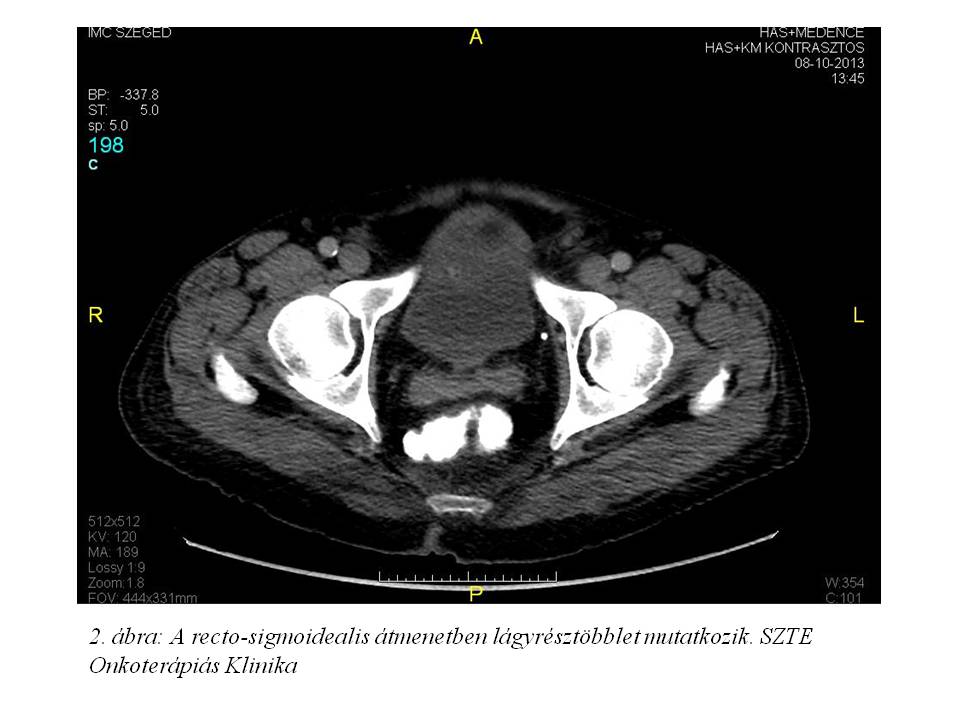

2013 októberében vérszékelés, hasi fájdalom, kb. 10 kg-os fogyás (10%-ot meghaladó súlyvesztés), emelkedő májfunkciós értékek (GOT: 65 U/l, GPT: 67 U/l, GGT: 631 U/l, ALP: 580 U/l, sebi: 34.5 umol/l, dibi: 25.5 umol/l) miatt indult kivizsgálása. Has-kismedence CT (2013.10.08., 1. ábra, 2. ábra, 3. ábra) készült, mely leírta a rectum-sigma átmenet lumenbe domborodó tumorát, multiplex máj metastasist, ascitest. Mellékleletként felvetette a jobb tüdő bázison lévő metasztázis gyanúját. Colonoscopia (2013.10.11.) során a sigmában, az anusgyűrűtől 25 cm-re egy vastag nyélen lévő 6-7 cm-es polyp volt látható. Mivel nem tűnt invazív tumornak, az SZTE Sebészeti Klinikán polypectomiát végeztek. A szövettan azonban malignusan transformálódott tubulovillosus adenomát igazolt adenocarcinomával (pT1). A T1-es kategóriájú daganat multiplex áttétképzését a beteg immunszuprimáltsága magyarázza.